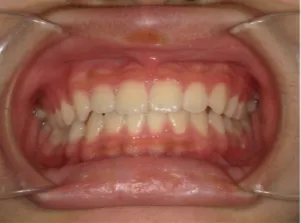

治療後⑧小6(12y3m):モノブロック装置継続中

治療後⑨中2(13y11m):モノブロック装置継続中

咬み合せも安定していて、口元の突出・口唇閉鎖不全も改善

*レントゲンや歯の萌出状況などから成長が終了していると考えられるため、現在残っている隙間や上下正中の不一致を改善するためマルチブラケット法へ移行するか検討中です。

治療は歯並びや口元などの状態から非抜歯治療で行う予定です。